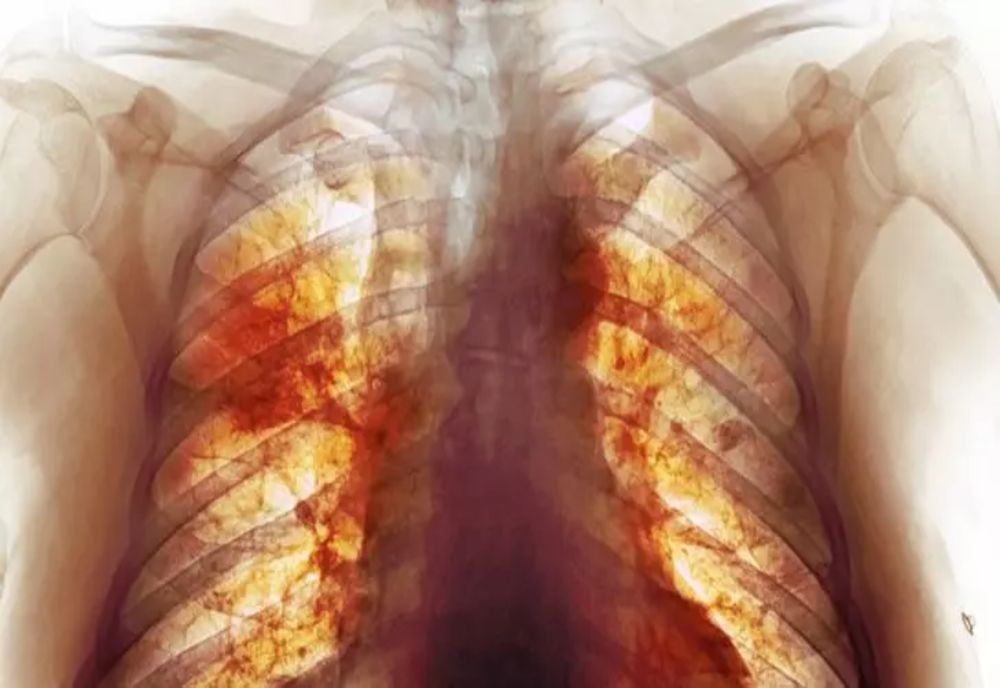

3 feb. 2022, 09:33ActualitateAdevărata dimensiune a dezastrului Covid. Cea mai detaliată radiografie dezvăluie cum arată, de fapt, plămânii după infectare - FOTO